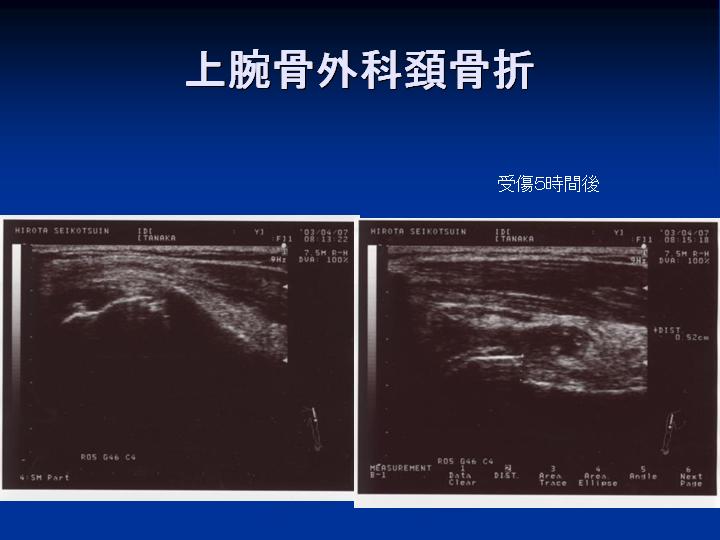

超音波(エコー)検査

当院では、外傷部(骨折疑い、捻挫、打撲、捻傷、肉離れなど)をエコー観察して施術計画を立てています。特に原因がわかりにくいお子様の痛みや怪我、治りにくいスポーツ障害でお悩みの方にお勧めします。詳細はこちらです。

参考資料 症例